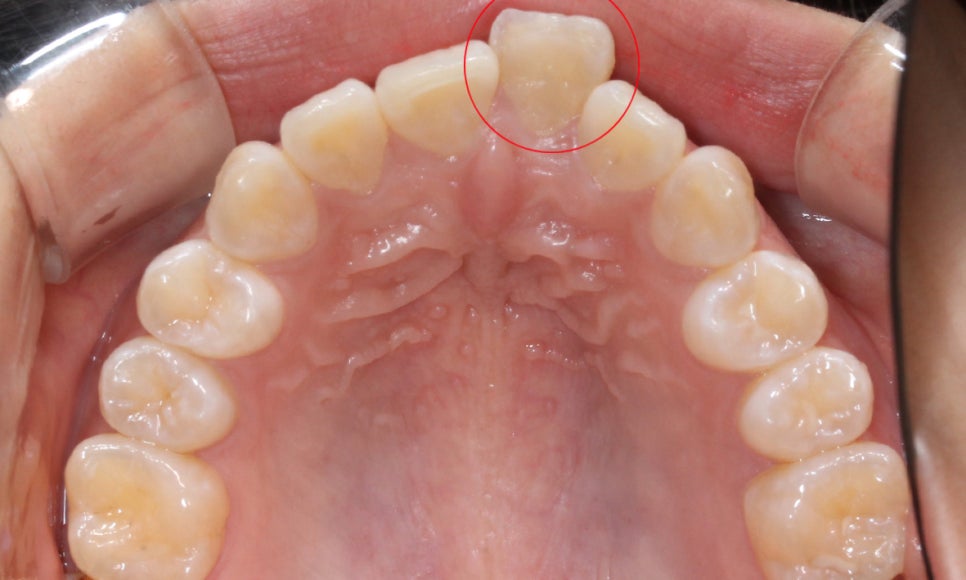

다음으로 상악과 하악의 교합면을 보시면

상악과 하악이 맞닿지 못하고 떨어져 있는 모습으로

구치부가 교합되고 있음에도 전치부 치열은 정확히

물리지 않는 모습인데요,

21번 치아가 순측으로 돌출되어 있기 때문에

앞니돌출 증상을 해결하고 전치부의 절단능력을

바르게 사용할 수 있도록 교정해야 합니다.

상악의 경우 교합면을 보시면

중절치의 뻐드러짐으로 인해

안모의 형태가 삐뚤어진 모습을 확인할 수 있습니다.